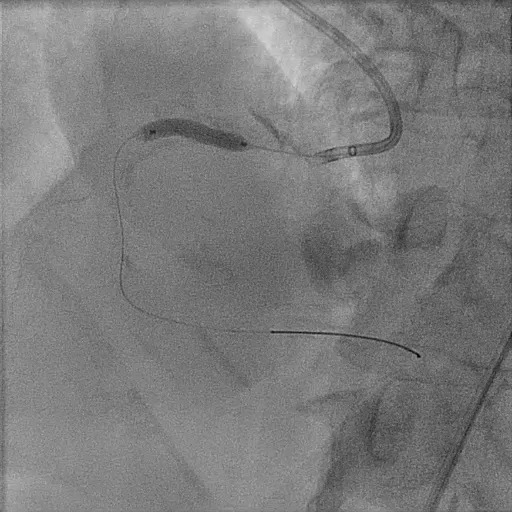

Change tp 1.5x15mm ballon to rate burst. Unable to cross IVUS catheter in. Predilate 2.5x15mm wire high pressure. Proceed with Lithix ballon 3.5x14mm preparation from distal to proximal RCA , multiple time ( distal 8atm x 3 , proximal 10-12 atm multiple slow inflation. Post Lithix , angiogram show good TIMI3 flow, mild linear dissection noted , good preparation. We proceed with 1xDCB over distal RCA and 1x DCB over midRCA 4.0X30 at 9atm. Post DCB noted recoil over distal RCA , then proceed with 1XDES 4.0x34 at 12atm at distal RCA. prox RCA treated with 1x DES till ostial RCA 4.0X34mm at 12atm. IVUS run post PCI , good stent expansion and opposition. Angiogram Post stent good TIMI 3 flow , no recoiled , accepted linear dissection . Patient well post PCI discharge well the next day.

Case Summary